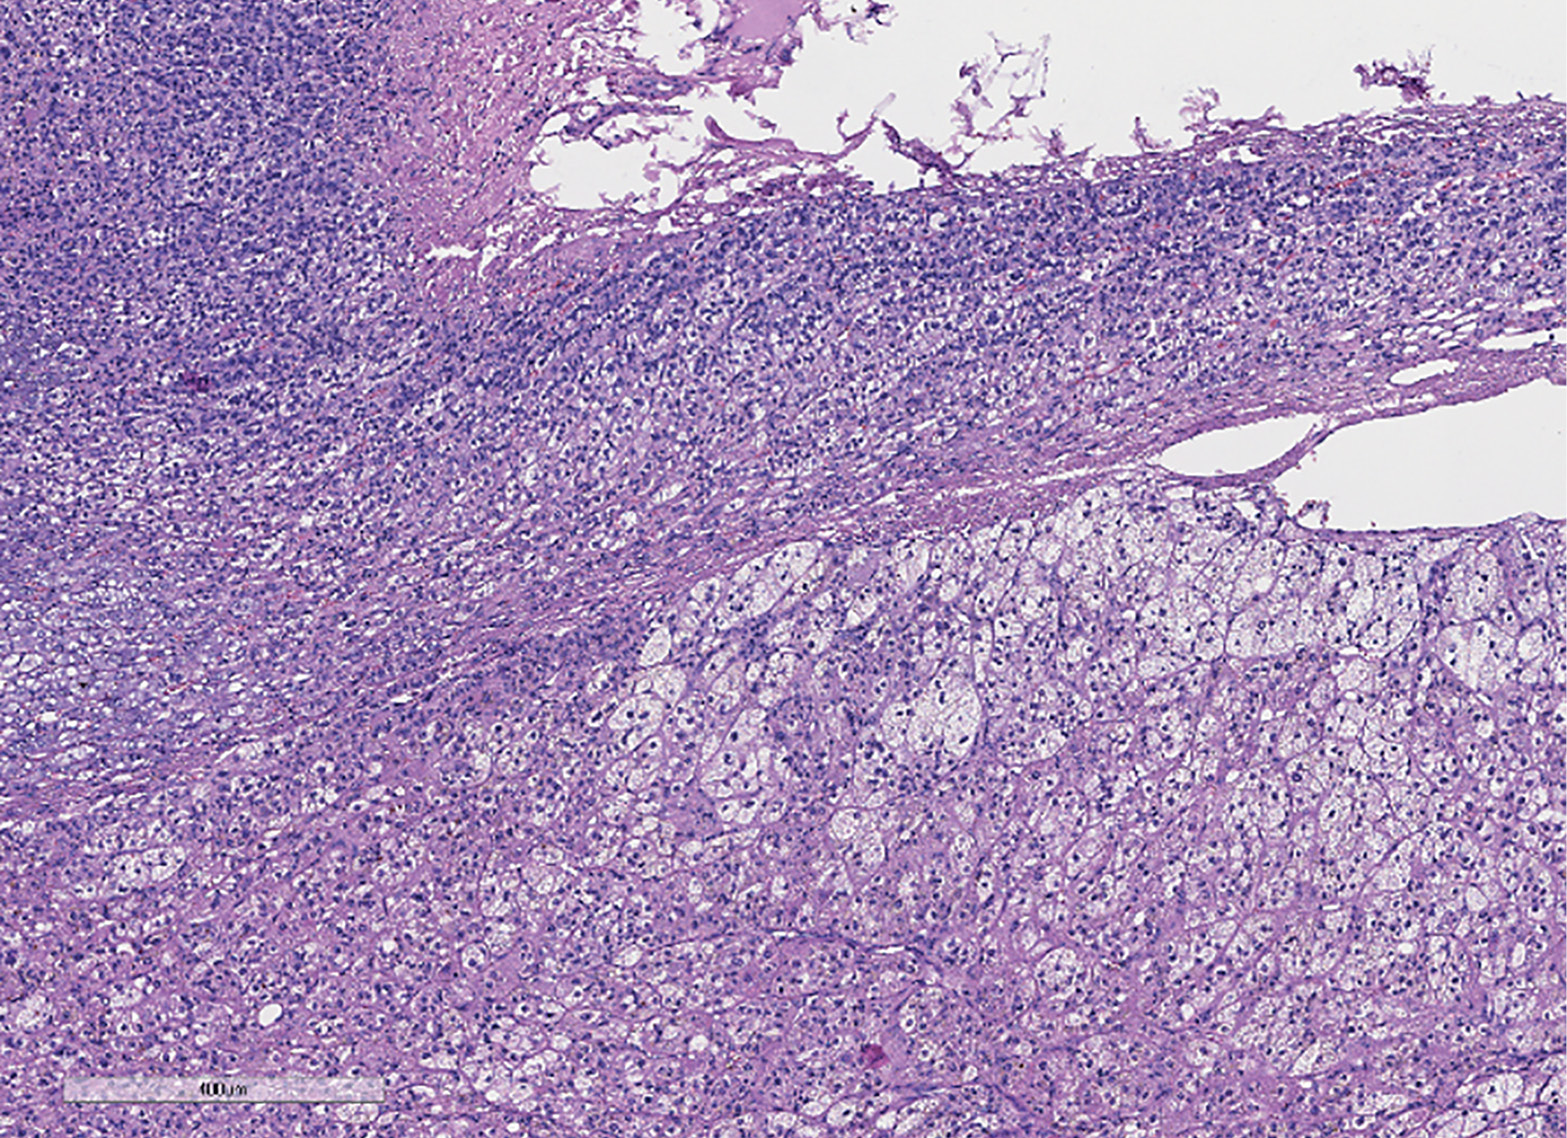

Гистологическая картина удаленной опухоли соответствует смешанноклеточной аденоме коры надпочечника (по системе Weiss — 0 баллов). На рис. 2 представлено микроскопическое строение опухоли. При иммуногистохимическом исследовании (ИГХ) выявлена позитивная реакция опухолевых клеток с меланом А, ингибином α и SF1, индекс пролиферации Ki67 составил 5,6%.

Рисунок 2. Данные патоморфологического исследования надпочечника. К надпочечнику неравномерной толщины прилежит неинкапсулированная четко отграниченная опухоль из компактных клеток и клеток с оптически «пустой» цитоплазмой, трабекулярного или альвеолярного строения (окраска гематоксилином и эозином х400).

Figure 2. Histopathological study of the adrenal gland. An unevenly thickened adrenal gland is adjacent to a non-encapsulated, well-demarcated tumor consisting of compact cells and cells with optically «empty» cytoplasm, with a trabecular or alveolar structure (stained with hematoxylin and eosin, x400).

2. Рисунок 2. Данные патоморфологического исследования надпочечника. К надпочечнику неравномерной толщины прилежит неинкапсулированная четко отграниченная опухоль из компактных клеток и клеток с оптически «пустой» цитоплазмой, трабекулярного или альвеолярного строения (окраска гематоксилином и эозином х400).